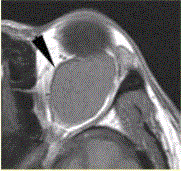

患者女,30岁,左眼球突出,运动障碍7个月。MRI平扫示左肌锥内等T信号影(下图)。增强扫描示均匀增强,眼肌、眼环正常。下述眼眶病变中,属于肌...

问题 患者女,30岁,左眼球突出,运动障碍7个月。MRI平扫示左肌锥内等T信号影(下图)。增强扫描示均匀增强,眼肌、眼环正常。 下述眼眶病变中,属于肌锥外病变的是